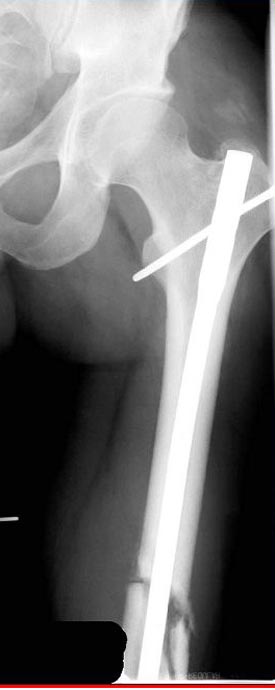

Деформация:

Вальгус- 17 градусов

Рекурватум 5 градусов

Укорочение 2.5см

Ротационно 22 градусов внутренная

Смещение диафиза по поперечнику 75%

Из трех вариантов:

Рассверливание с заменой более большого диаметра штифтом,

Остеотомия с фиксацией пластиной+костная пластика,

Аппарат Илизарова= Taylor spatial frame

Гвоздь для ротационных смещениц был бы идеальнымимплантом, после коррекции есть возможность блокировать, но из-за укорочения метод оставил на последнее место. Есть метод Сhaplan лечения ложных суставов бедра, где необходимость bone graft, накладывается феморальный дистрактор и после удаления штифта - рассверливание, через проксимальный канал вводят костный графт в место ложного сустава под рентген контролем, потом вводят штифт, кстати, само рассверливание дейстивует как стимулятор - активизирует восстановительный процесс.

Обычный мой первый выбор - вариант с пластиной, - учитывая бывшую инфекцию, открытую травму, посчитал метод менее приемливым.

Еще больной был противв костной аутопластики, да и самому тоже хотелось перейти к истокам "откуда мы" более усовершенствованному Курганскому методу.

Операцию провели в два этапа, сперва удалили штифт, рассверливание римером на пару мм большего диаметра, определение чувствительности на анаэробную и аэробную культуру (где исследования показали негативный результат чувствительности), через дней десять - начали аппаратную фиксацию.